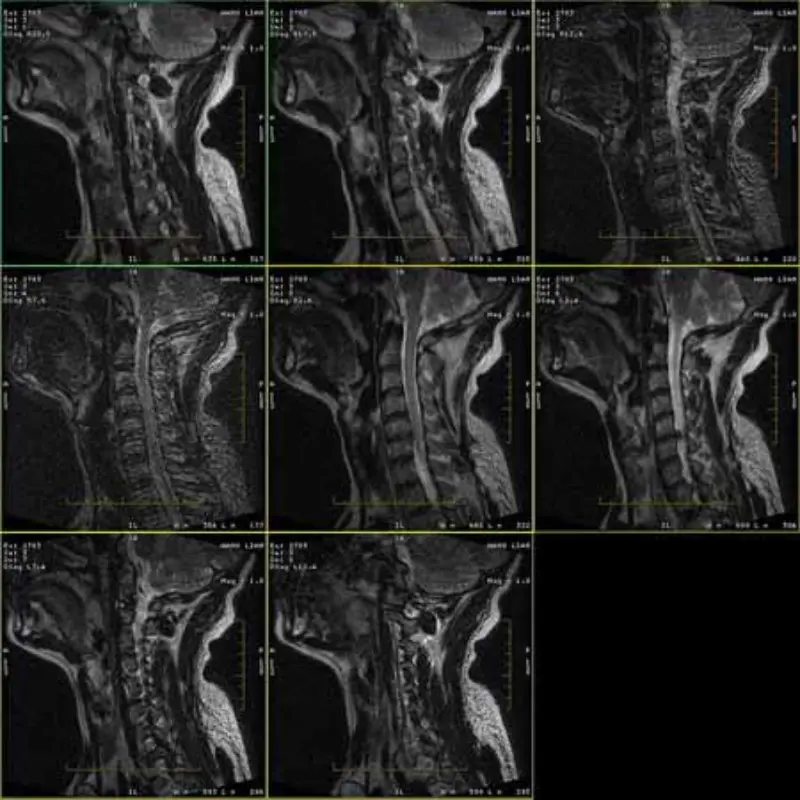

Imej protokol FRFSE dan GRE mempunyai hantu dan kadangkala imej SNR rendah muncul dalam satu siri. Tetapi imej protokol SE adalah perkara biasa.

Sila lihat lampirkan gambar.